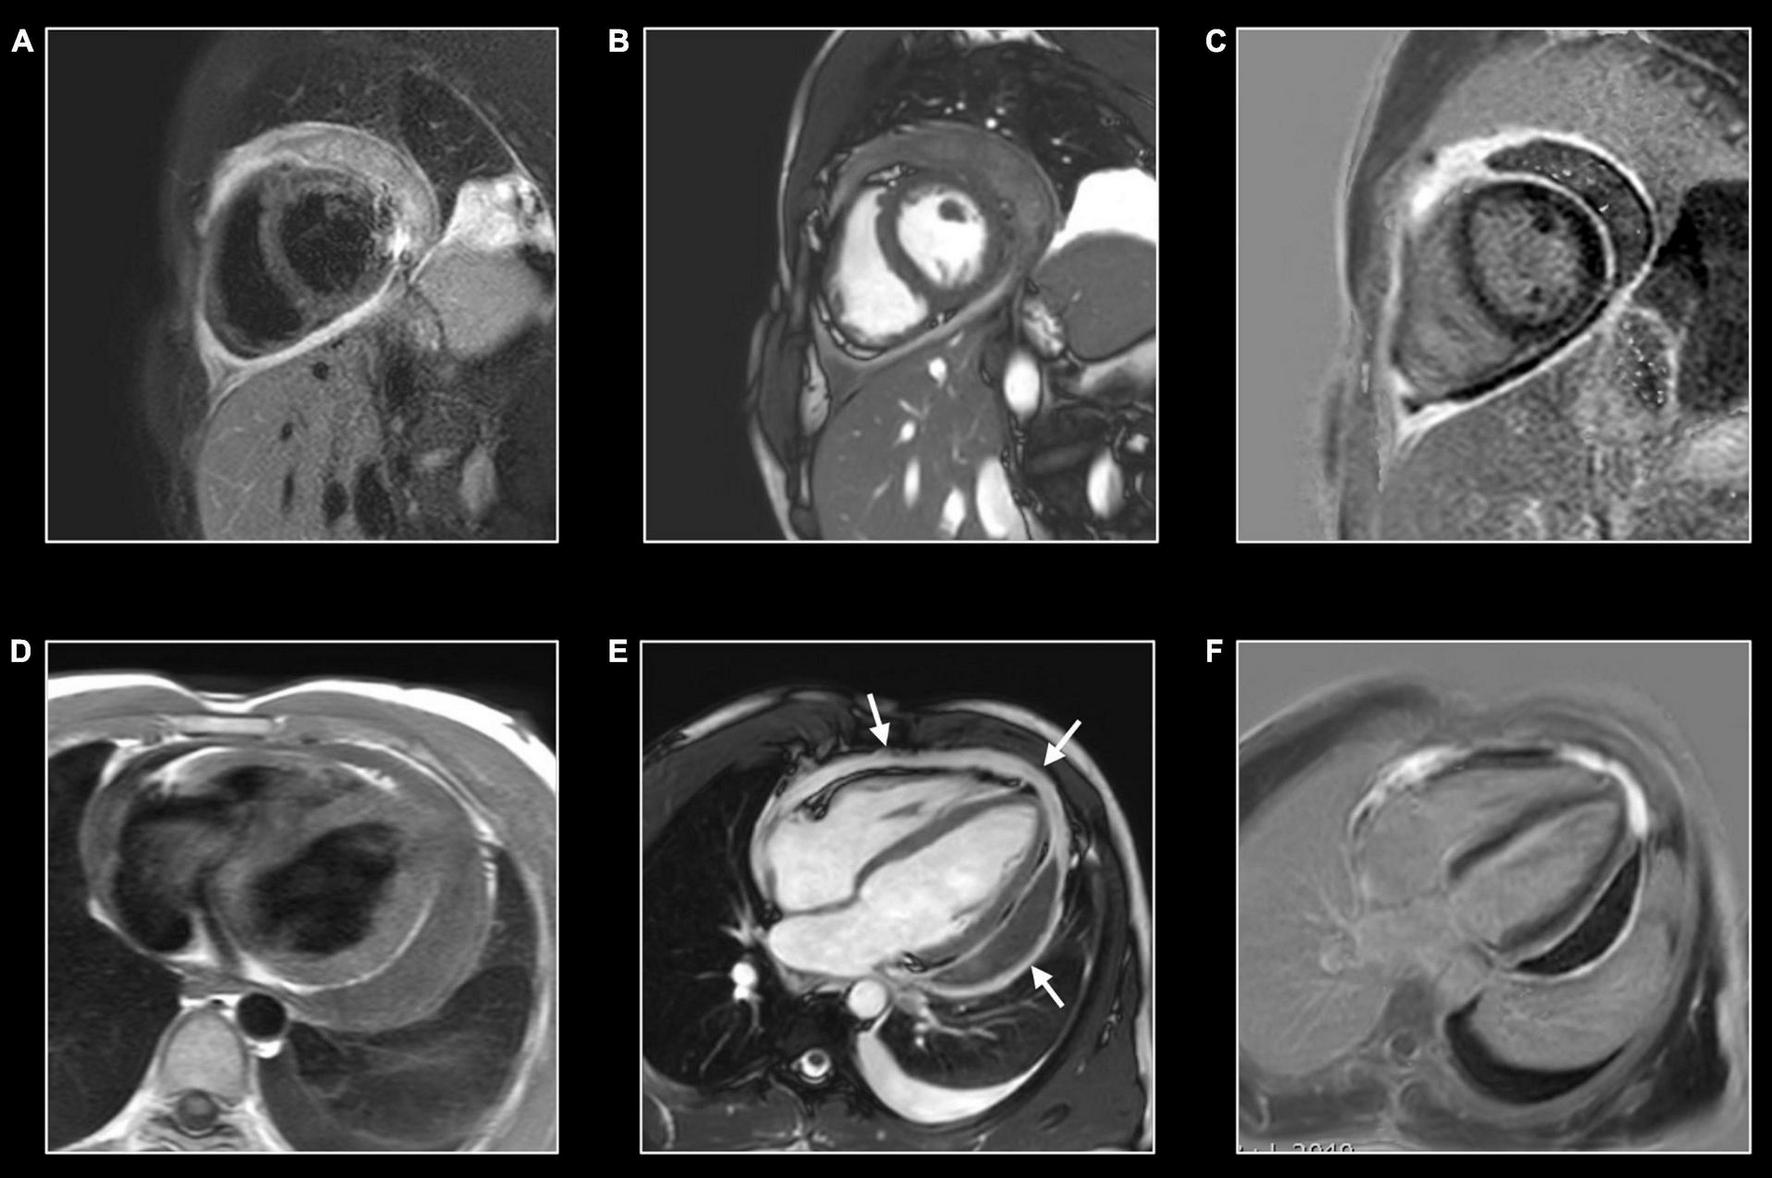

FIGURE 6

Giant cell myocarditis rapidly evolving to heart failure. Forty-six-year-old woman presenting with monomorphic ventricular tachycardia arising from the basal septum. Transthoracic echocardiography shows mildly decreased LV function (EF 49%) with dyskinetic basal septum. CMR shows mildly dilated and dysfunctional left ventricle (LVEDVi 107 ml/m2 – LVEF 45%), and thinned, dyskinetic basal septum. T2w-imaging (A) shows myocardial edema in the basal part with strong increase of native T1 (i.e., 1,230 ms) and T2 (i.e., 99 ms) relaxation times in this area [arrows (B,C), respectively]. Strong uptake of contrast showing a non-ischemic enhancement pattern but in a large extent completely transmural [arrows, (D)] and increased ECV (i.e 65%) (not shown). Findings suspected of active inflammation in the basal septum with local adverse remodeling. A left-sided myocardial biopsy showed giant cell myocarditis. Follow-up CMR, one month later, showed important deterioration of LV function (LV EF 26%). Because of the unfavorable outcome, the patient received a cardiac transplant. Two years later, she is doing well.

Inflammation has been proposed as a key factor in many other cardiovascular diseases, especially those characterized by myocardial injury. Different grades of myocardial inflammation have been demonstrated by endomyocardial biopsy in patients with sarcomeric hypertrophic cardiomyopathy and associated with MRI-proven myocardial fibrosis (Figure 12) (73). Evidence supporting the role of the inflammatory process in atherosclerosis accumulated in recent years. Moreover, activation of the inflammatory pathway was proven in patients with acute myocardial infarction not only in injured segments but also in areas of remote myocardium (74). Targeting inflammatory pathways with specific therapies was proven to improve LV remodeling in preclinical studies but failed in reaching significant outcomes in clinical ones (75). Recent evidence suggests the role of inflammation as a driver for phenotypic expression in patients with arrhythmogenic cardiomyopathy (76). Increased susceptibility to viral infection and immune activation may act on top of genetic predisposition. Moreover, myocarditis has been proposed as an additional criterion for arrhythmogenic cardiomyopathy (77). Further studies using non-invasive imaging for the assessment of inflammation in these settings are needed. As mentioned above, allograft rejection after heart transplant is a specific form of inflammatory myocardial disorder (9). Here too, CMR may add valuable information in addition to the endomyocardial biopsy (Figure 13).

FIGURE 12

Myocardial inflammation in hypertrophic cardiomyopathy. Forty-seven-year-old man with familial hypertrophic cardiomyopathy (PRKAG2 mutation). All images were obtained in mid-ventricular short-axis. Thickened ventricular septum (max 20 mm) [cine image, (C)]. Focal small area of increased native T1 [arrows, (A)] and T2 values [arrows, (B)] in the thickened anteroseptal LV wall, closely corresponding to the area of myocardial fibrosis at LGE imaging [arrows, (D)]. These findings confirm the presence of concomitant myocardial edema in the fibrotic myocardium.

FIGURE 13

Allograft rejection. Twenty-two-year-old woman with history of univentricular heart, re-transplantation in 2021, and clinical evidence of acute rejection. CMR shows diffuse increase of native T1 (A) and T2 (B) myocardial values, most pronounced on the right side of the ventricular septum extending to the anterior/posterior atrioventricular groove [black arrows, (A,B)], and in the right ventricular (RV) wall [white arrows, (A,B)]. LGE imaging shows strong enhancement in RV wall, subepicardial left ventricular wall, and right side of the ventricular septum extending to the anterior/posterior atrioventricular groove [arrows, (C,D)]. Endomyocardial biopsy shows acute cellular rejection with diffuse extensive lymphocytic and eosinophilic inflammation [grade 3A (IHSLT 1990)–grade 2R (IHSLT 2004)], and myocardial fibrosis.